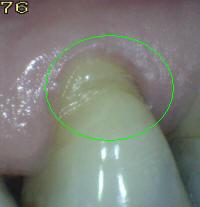

Código E: Si la superficie de la raíz no puede ser visualizada directamente como resultado de la falta de la  recesión gingival, entonces es excluida. Ver imagen inferior izquierda.  Superficies cubiertas completamente por cálculos deben ser removidos antes de determinar el estado de la superficie.